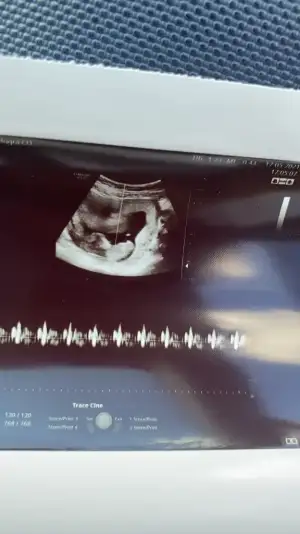

Ikra meyra Ikra meyra merhabaaa Canım :) Arkadaşımın bebisinin fotosunu atiyorum.Sana zahmet tahminde bulunabilirsen çoooook sevinirim :) Şu an 12+2 :)

Eklentiler